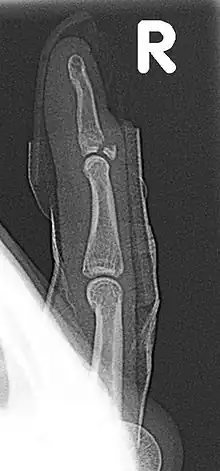

| Fracture of the dorsal base of the distal falange by extensor tendon avulsion (Busch fracture) | |

In medicine a Busch fracture[1] is a type of fracture of the base of the distal phalanx of the fingers, produced by the removal of the bone insertion (avulsion) of the extensor tendon. Without the appropriate treatment, the finger becomes a hammer finger. It would correspond to the group B of the Albertoni classification.[2] It is very common in motorcycle riders and soccer joggers, caused by hyperflexion when the tendon is exercising its maximum tension (the closed hand tightening the clutch lever or the brake lever).[3][4]

The mechanism of this injury can be described as an avulsion of the tendon fixed to the distal phalanx.[6][7][8]